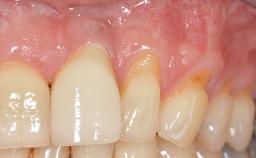

It is sometimes necessary to remove and replace compromised implants. This case is a clear example of the need for multiple steps to achieve an optimal therapeutic result for patients with non-salvageable implants. It illustrates how the lost soft and hard tissues were rebuilt in a sequence that improved the healing of the hard tissues and assured their long-term stability. The 35-year-old healthy patient presented with clinical attachment loss on the proximal and lingual surfaces of the natural dentition. Some gingival recession was present on natural teeth, particularly in the posterior sextants (S1, S3, S4, and S6).

Soft Tissue Anatomy Intact Defective

Bone Volume Horizontally and vertically sufficient Horizontally deficient Deficient vertically or deficient vertically AND horizontally